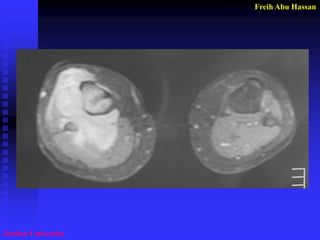

Site of the biopsy

Extra Osseous Component

of the Tumor, Why????

* >Dx (Center necrosed)

* To avoid #.

* F.S. can be done quickly.